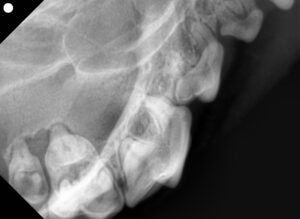

- レントゲン検査では 歯槽骨の融解はなし

つまり「歯肉炎」の段階で、まだ「歯周病」には進行していませんでした。